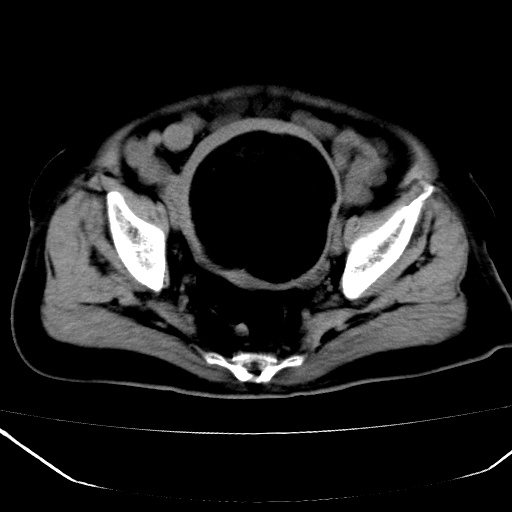

标题: CT18557:盆腔内包块,请指教

患者,女,74岁,无不适,b超示盆腔包块。

子宫前上方巨大脂性肿物,肿物边缘为较厚软组织密度影,其内缘欠光整,脂性密度中央见结节状软组织密度影“漂浮”,肿物与子宫前壁关系密切,考虑1脂肪瘤2皮样囊肿3肌瘤脂样变

ct值-90hu